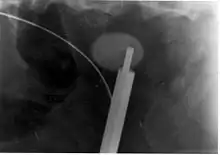

A lithotriptor machine with a mobile fluoroscopic system ("C-arm") is seen in an operating room; other equipment is seen in the background including an anesthesia machine.

Extracorporeal shock wave lithotripsy (ESWL) is a noninvasive technique for the removal of kidney stones. Most ESWL is carried out when the stone is present near the renal pelvis. ESWL involves the use of a lithotriptor machine to deliver externally applied, focused, high-intensity pulses of ultrasonic energy to cause fragmentation of a stone over a period of around 30–60 minutes. Following its introduction in the United States in February 1984, ESWL was rapidly and widely accepted as a treatment alternative for renal and ureteral stones.[95] It is currently used in the treatment of uncomplicated stones located in the kidney and upper ureter, provided the aggregate stone burden (stone size and number) is less than 20 mm (0.8 in) and the anatomy of the involved kidney is normal.[96][97]